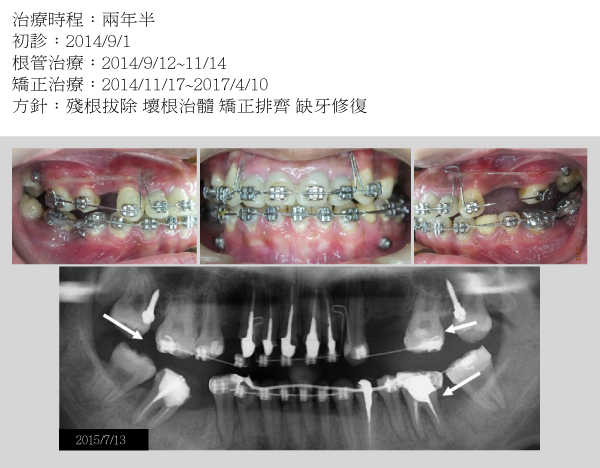

案例一

幸福人生從齒起

健齒養顏 開心樂活

天泉專科團隊協同診治 求精求速